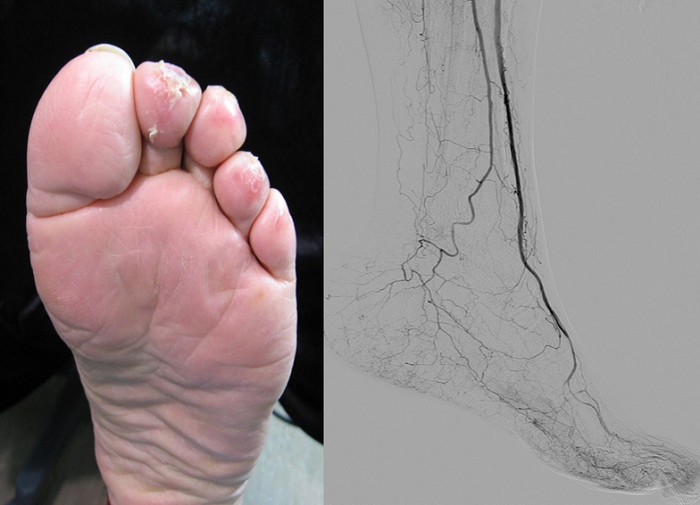

당뇨병성 신부전 환자의 발과 발동맥 사진. 점점 괴사가 진행되고 있는 상태

위는 발가락의 괴사가 점점 진행되고 있는 당뇨병성 신부전환자의 발과 발동맥사진입니다. 둘째와 넷째 발가락의 일부는 검게 되사되었고 나머지 발가락들에도 염증이 퍼져 있습니다. 발 동맥사진을 보면 발 등과 발 바닥으로 주행해야 할 정상적인 동맥은 다 막혀있고 발목에서 꼬불꼬불하게 이어지는 샛길 동맥만 어렵게 보입니다.